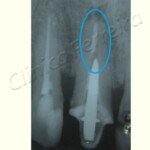

Geralmente, sê num primeiro tratamento, não foi possível seguir os padrões exigidos: limpeza (remoção de todos os microorganismos), preenchimento correto do canal com o material obturador, etc. Essas incorreções podem provocar lesões na ponta da raíz (periápice) do tipo abcessos e lesões crônicas, havendo a necessidade de um novo tratamento, ou seja, um retratamento do dente afetado. Desde que bem executado, este tratamento é eficiente.